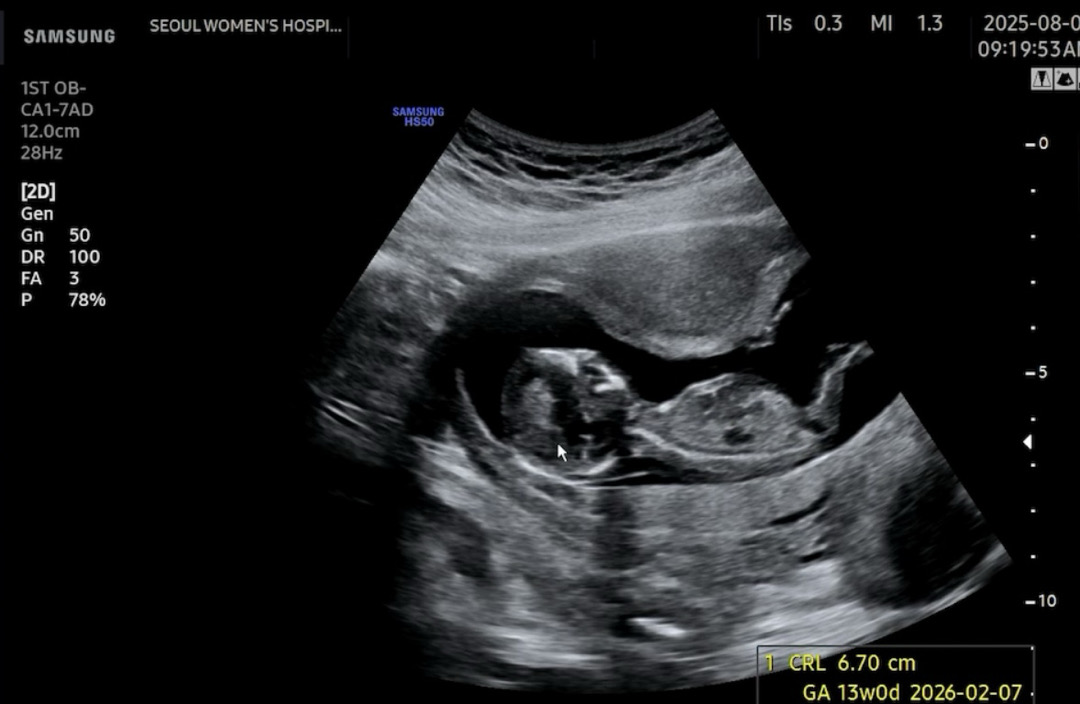

한달만에본 13주차 울아이👶🏻남자일까여 여아 일까여 뭔가 달린걸 다른각도에서 봤던거 같은대..

생식기가 안 보이는 사진 같아요! 다른 사진 없을까요??

사진이 하나밖에 안올라가기도 하고 영상이라 어떤부분에서 생식기인지 몰르겠네요 ㅠㅠ

이걸론 안될까요?

그리고 이게 발바닥?밑에서 위로 찍은각도고 중간에 점이 생식기 아닐까요?

12주차에는 남녀 다 생식기가 튀어나온 모양이라서 옆에서 생식기 보이게 찍은 사진이 필요해용 ㅠㅠ 이거는 저희 아이 초음파 사진인데 흰색으로 표시한 저 척추랑 생식기 각도를 보는 거예요!